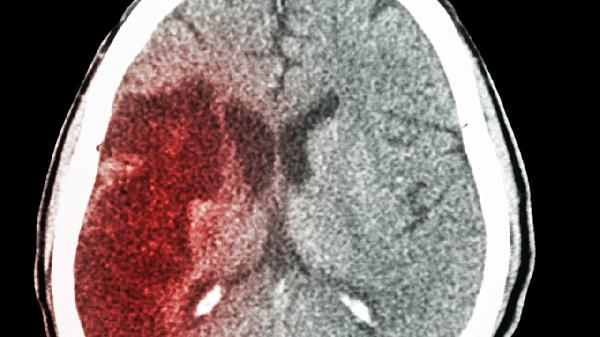

大多数轻微脑出血并不会立刻威胁生命,但仍然需要留意病情是否加重。它的严重程度主要由五个方面决定:出血量、出血位置、基础疾...

外伤引发的脑出血,可以通过维持呼吸道畅通、控制血压、减轻颅内压力、手术干预以及康复锻炼等手段进行治疗。这种类型的脑出血通...

脑出血患者通常会根据出血量和病情严重程度,选择开颅血肿清除术或微创穿刺引流术。目前常用的手术方式包括:开颅血肿清除术、微...